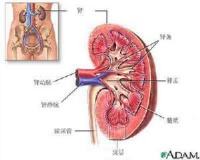

肾错构瘤

肾错构瘤又称肾血管平滑肌脂肪瘤,为良性肿瘤。近年来发病率有增高趋势,可能与诊断技术水平提高有关。肾错构瘤可以是独立的疾病,也可能伴有结节性硬化,后者是一种家族遗传性疾病。临床特点为双肾多发病灶,合并智力发育迟缓,面部蝴蝶状皮脂腺瘤等。女性多见,发病年龄多为20-50岁。但我国肾错构瘤患者绝大多数并不伴有结节性硬化。

肾错构瘤

肾

血管平滑肌脂肪瘤(肾错构瘤)可伴结节性硬化,此系常染色体显性基因,是遗传的家族性疾病,80%病人脸部有蝴蝶状皮脂腺瘤,其他器官如脑、眼、骨、心、肺亦有病变。大脑发育迟缓、智力差、有癫痫发作,多为双肾多发病源。中国血管平滑肌脂肪瘤绝大多数并不伴有结节性硬化,80%为女性,出现病状在20-50岁,40岁以后占多数。肾错构瘤是一种常见的肾脏良性肿瘤,其治疗方法和预后直接与肿瘤大小、生长速度、与肾实质的关系等有关。现回顾性分析1997年5月~2005年12月收治的22例肾错构瘤患者的临床资料,以探讨肾错构瘤的诊治方法。